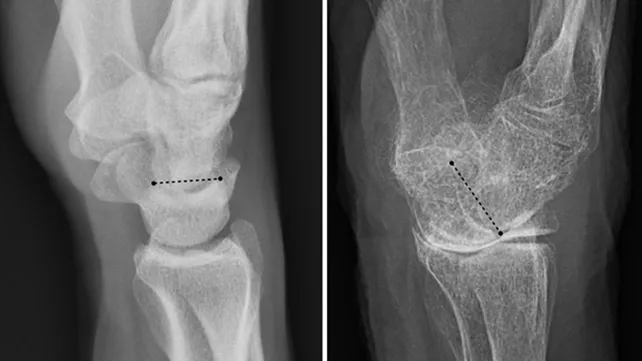

La Organización Mundial de la Salud la define como una afección caracterizada por una baja masa ósea y deterioro de la microarquitectura del tejido óseo, que conduce a un aumento de la fragilidad del hueso y consecuentemente a un mayor riesgo de fracturas.

Según los especialistas, hasta aproximadamente los 30 años, una persona normalmente construye más hueso del que pierde. Después de los 35 años, la destrucción de hueso supera la construcción, y resulta una pérdida gradual de la masa ósea. Cuando esta pérdida llega a cierto punto, la persona padece osteoporosis.